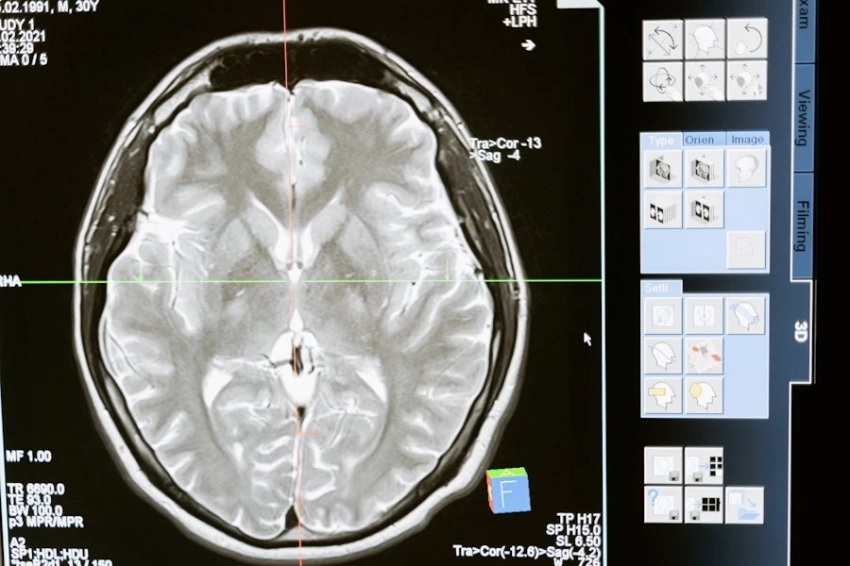

Ученые сосредоточили внимание на глиомах - одних из самых агрессивных форм опухолей мозга. Особую опасность представляют глиобластомы четвертой стадии, при которых пациенты живут в среднем от 9 до 12 месяцев после постановки диагноза. От этой формы рака ушли из жизни такие известные деятели культуры, как Дмитрий Хворостовский и Анастасия Заворотнюк.